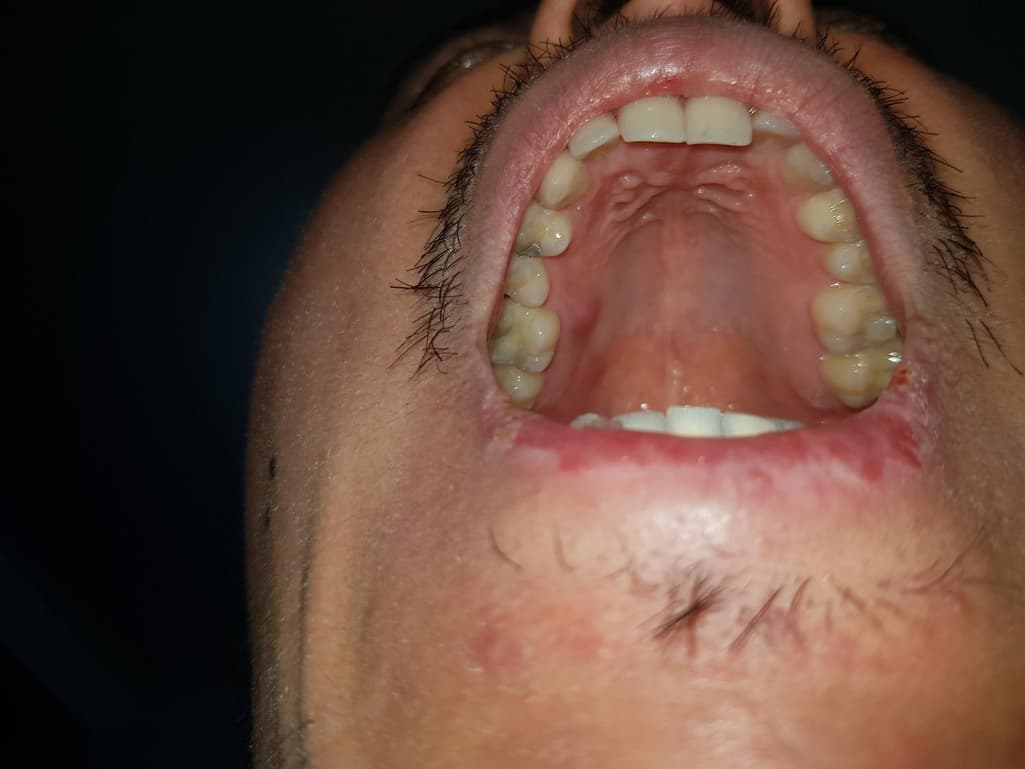

갑자기 생긴 이 입천장 물집이 치료가 되고 있는걸까요?

2월 13일 잇몸치료를했고 2월 20일 깨진 3년된 아말감을 레진으로 교체후 사진입니다

그리고 갑자기 이런 혹이 20일에 생겼습니다 통증이 없고 말랑했습니다

3월될때까지도 물렁하며 항상 크기변화없이 똑같았습니다

3월 7일의 사진인데 3월 6일에 불편감때문에 저녁양치후 포크로 뜨거운물 에탄올소독후 살짝찔렀습니다